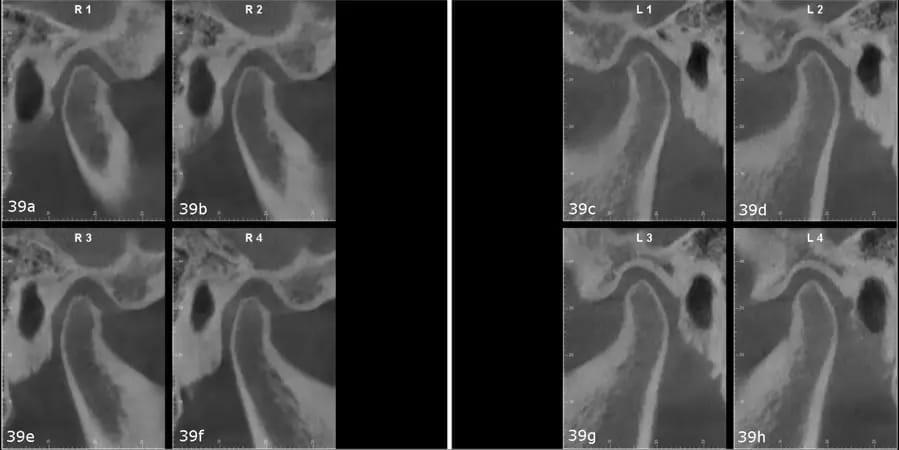

Пациентка пожаловалась на боли в суставах и орофациальных мышцах, головные боли, боли в шее и ночной бруксизм. На КЛКТ были видны небольшие мыщелки с уплощенными суставными поверхностями. Правый мыщелок был расположен немного назад в нижнечелюстной ямке (фото 39). Кроме того, виртуальный артикулятор с использованием системы MODJAW показал, что существует значительное расхождение между максимальным смыканием и центральной окклюзией и что первый окклюзионный контакт произошел на зубе №27 (фото 40).

Фото 39a–h: Сагиттальные изображения височно-нижнечелюстного сустава, полученные при КЛКТ-сканировании.